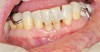

Figure 2  Postmetastatic cancer patient with BRONJ (A) in the lower right quadrant and (B) in the lower left quadrant.

Figure 2

Figure 3  Postmetastatic cancer patient with BRONJ (A) in the lower right quadrant and (B) in the lower left quadrant.

Figure 3

For patients on IV bisphosphonates, after bone is exposed, it is almost impossible to cover.15 Most cases worsen if surgical intervention is performed. Most patients must simply deal with the exposed bone and keep it clean so that bacterial infection does not occur. Figure 2 and Figure 3 show a postmetastatic prostate cancer patient with exposed bone. The treatment plan for this patient was to make a soft-lined denture that would not put pressure on the exposed bone and to check for bacterial infection on a routine basis. When dealing with patients on or about to begin IV bisphosphonate therapy, dentists need to be very astute. As stated earlier, this form of the drug has a much higher incidence of complications. These patients are often very sick and immuno-compromised and, therefore, must be managed properly. Pre-IV bisphosphonate patients (ie, those not yet receiving the drug) are much easier to manage than patients already receiving the drug. First, ask the treating physician, usually an oncologist, if he or she can wait 2 months before the drug is given. If the cancer is severe, it may not be possible to wait. Dental healthcare provides should make use of whatever time can be made available before bisphosphonate treatment begins.16 This time should be used to get a full-mouth series of radiographs and to remove all dental infections, including all decay. If decay cannot be removed completely, the tooth should be considered for extraction. Before IV therapy begins, patients are at a lower risk for extraction complications than they are during bisphosphonate therapy.